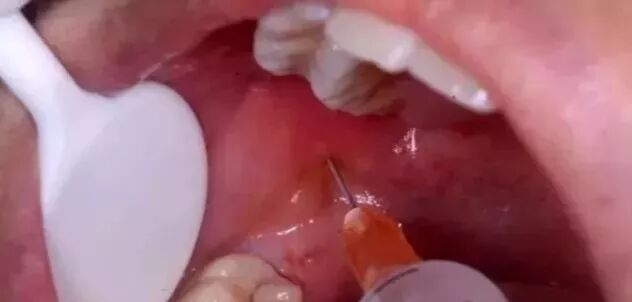

拔牙时打麻药主要有两种方式:阻滞麻醉和浸润麻醉。

浸润麻醉是粘膜下注射或者牙周膜注射,局部仅有毛细血管,进入血液循环的微乎其微;

阻滞麻醉注射较深一些,但是退药前也会回抽看有无回血,以避免麻药进入小血管。极其微量的麻药进入血液循环也会很快代谢掉,并不会损伤大脑。